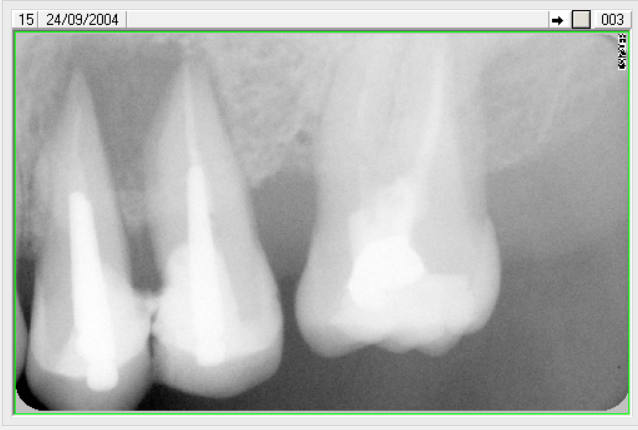

Femme de 71 ans................4 et 2 ans de recul ( les numéros de dents sont faux )

Capture d écran 2017 03 21 à 12.15 - Eugenol

lachmar

07/11/2017 à 18h05

CHIRDENT écrivait:

--------

> Femme de 71 ans................4 et 2 ans de recul ( les numéros de dents sont

> faux )

une seule chose à dire : bravo

Joli ! Mes respects c'est du beau travail.

Mais les lésions ne sont pas similaires à celles nous concernant, on a des paroies restantes même sur la seconde on peut le deviner rien que par la paroi mésiale et une apparence moins radoiclaire au niveau de la racine distale.

Celle-ci en effet pouvaient être sauvées (quoique j'aurai hésité sur la seconde mais pas la première de 2017).

Je ne mangerai donc pas mon davier pour cette fois. Mais encore une fois très beau travail !